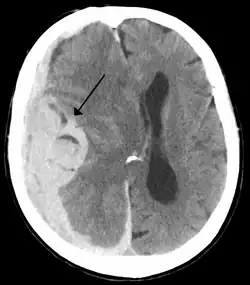

Midline shift is a shift of the brain past its center line.[1] The sign may be evident on neuroimaging such as CT scanning.[1] The sign is considered ominous because it is commonly associated with a distortion of the brain stem that can cause serious dysfunction evidenced by abnormal posturing and failure of the pupils to constrict in response to light.[1] Midline shift is often associated with high intracranial pressure (ICP), which can be deadly.[1] In fact, midline shift is a measure of ICP; presence of the former is an indication of the latter.[2] Presence of midline shift is an indication for neurosurgeons to take measures to monitor and control ICP.[1] Immediate surgery may be indicated when there is a midline shift of over 5 mm.[3][4] The sign can be caused by conditions including traumatic brain injury,[1] stroke, hematoma, or birth deformity that leads to a raised intracranial pressure.

Doctors detect midline shift using a variety of methods. The most prominent measurement is done by a computed tomography (CT) scan and the CT Gold Standard is the standardized operating procedure for detecting MLS.[5] Since the midline shift is often easily visible with a CT scan, the high precision of Magnetic Resonance Imaging (MRI) is not necessary, but can be used with equally adequate results.[5] Newer methods such as bedside sonography can be used with neurocritical patients who cannot undergo some scans due to their dependence on ventilators or other care apparatuses.[6] Sonography has proven satisfactory in the measurement of MLS, but is not expected to replace CT or MRI.[6] Automated measurement algorithms are used for exact recognition and precision in measurements from an initial CT scan.[7] A major benefit to using the automated recognition tools includes being able to measure even the most deformed brains because the method doesn’t depend on normal brain symmetry.[7] Also, it lessens the chance of human error by detecting MLS from an entire image set compared to selecting the single most important slice, which allows the computer to do the work that was once manually done.[7]

Three main structures are commonly investigated when measuring midline shift. The most important of these is the septum pellucidum, which is a thin and linear layer of tissue located between the right and left ventricles.[7] It is easily found on CT or MRI images due to its unique hypodensity.[7] The other two important structures of the midline include the third ventricle and the pineal gland, which are both centrally located and caudal to the septum pellucidum.[6][7] Identifying the location of these structures on a damaged brain compared to an unaffected brain is another way of categorizing the severity of the midline shift. The terms mild, moderate, and severe are associated with the extent of increasing damage.

Midline shift measurements and imaging has multiple applications. The severity of brain damage is determined by the magnitude of the change in symmetry. Another use is secondary screening to determine deviations in brain trauma at different times after a traumatic injury as well as initial shifts immediately after.[3] The severity of shift is directly proportional to the likeliness of surgery having to be performed. The degree of MLS can also be used to diagnose the pathology that caused it. The MLS measurement can be used to successfully distinguish between a variety of intracranial conditions including acute subdural hematoma,[5][7] malignant middle cerebral artery infarction,[3] epidural hematoma, subarachnoid hemorrhage, chronic subdural hematoma, infarction, intraventrical hemorrhage, a combination of these symptoms, or the absence of pertinent damage altogether.[7]